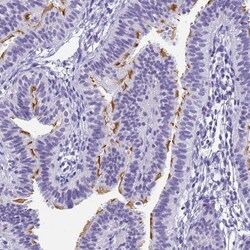

Immunohistochemistry

PA5-61223 IHC

Method:

Other validation